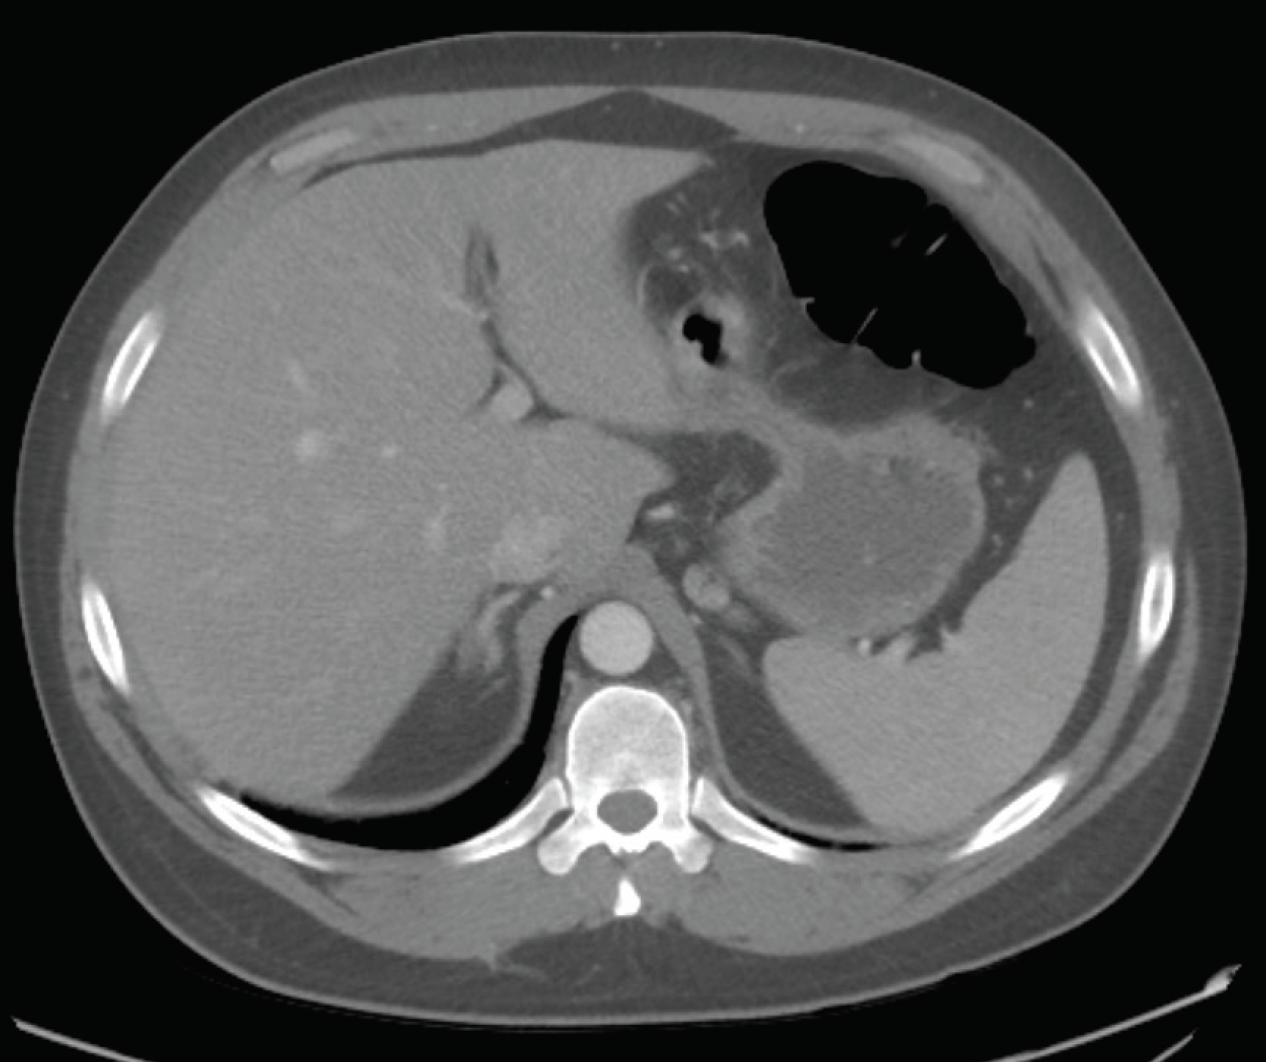

Osama Mukarram, MD; Ahmed Khan, MD; Mary Mok, MD; Adnan Haider, MD

A 33-year-old man presented with bilateral flank pain associated with nausea and vomiting 10 days after having undergone an uncomplicated laparoscopic cholecystectomy. He denied having had fever, chills,...